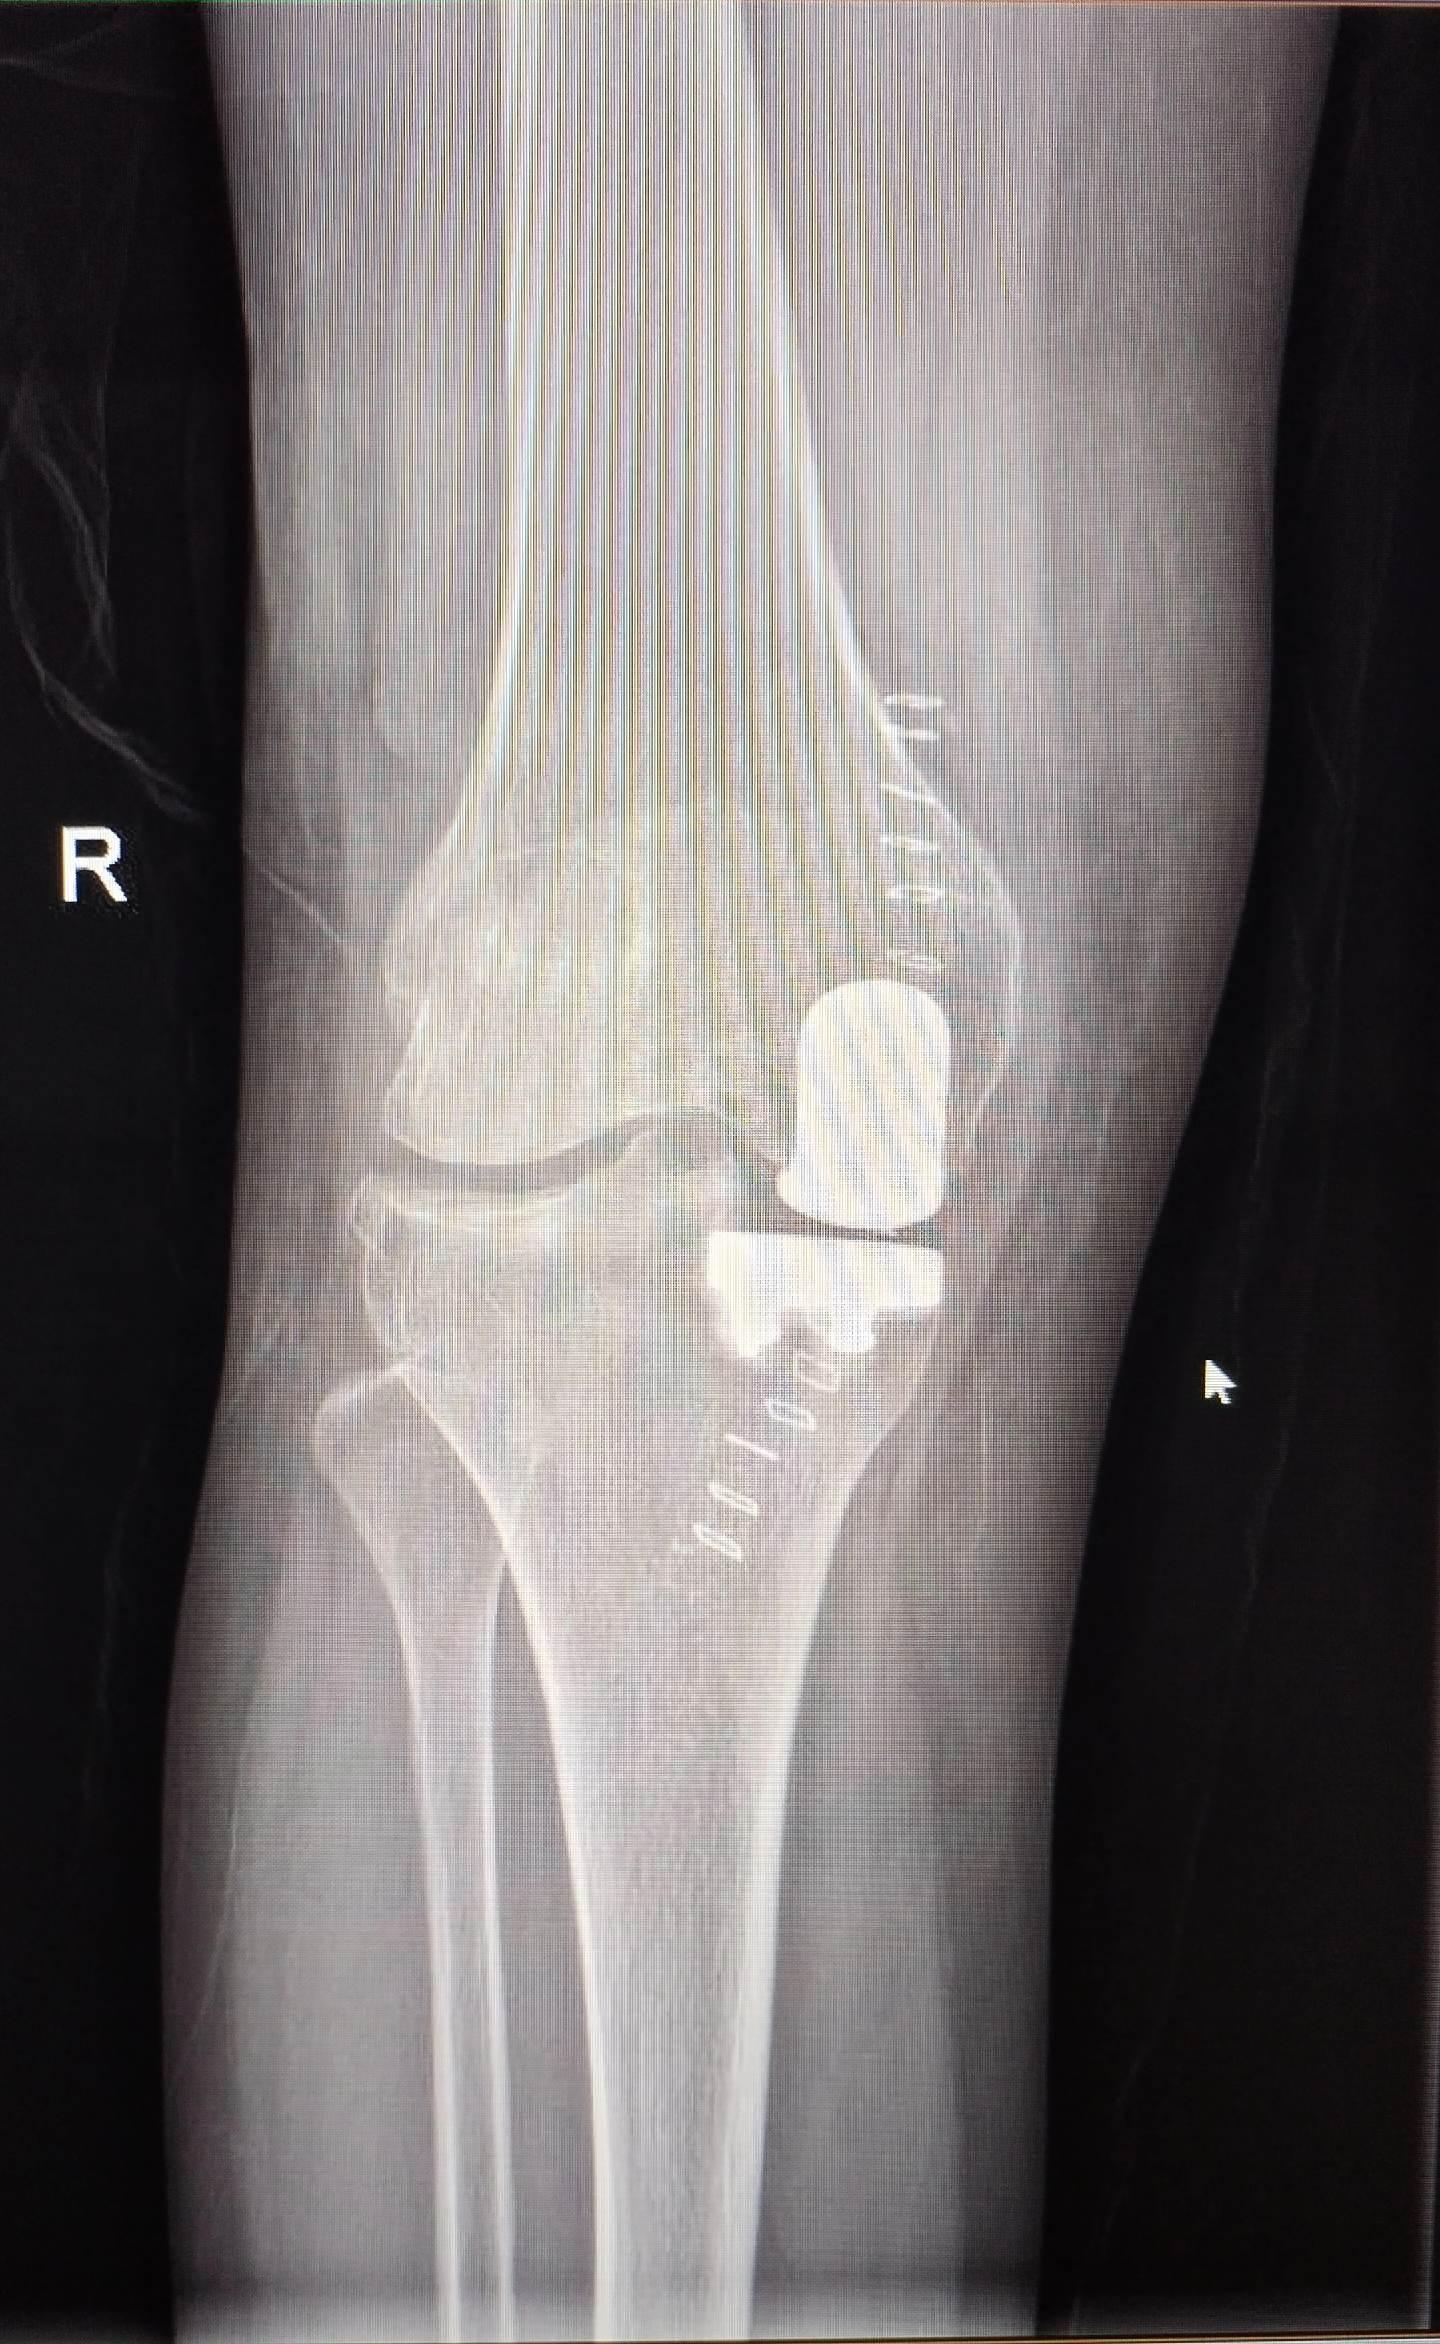

UKA单髁置换。膝关节骨关节炎,同期双侧单髁置换,术后四天出院,快速康复,省医关节外科🌹